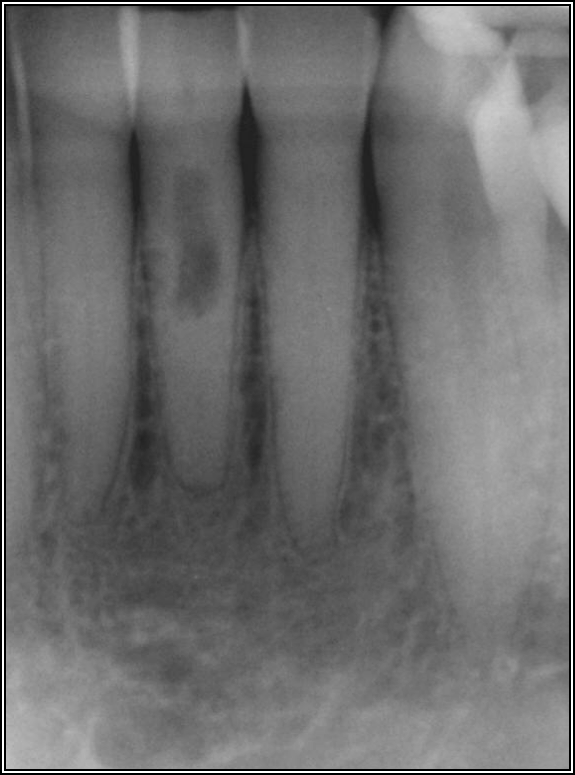

Figure 2 shows a situation where the clinician excavated the tooth of a patient with decay, and it pulped out. The buccal and lingual walls were intact; however, the walls were minimal, and there were still fragments of amalgam and cracks. If the clinician prepared this tooth after building it up, the clinician would lose all the good tooth structure that was left. This tooth would likely need a post.

Fig 2. Minimal walls.

Figure 2